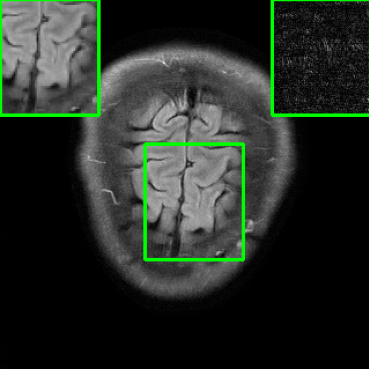

Results for the FastMRI Brain Dataset: we present the robustness results of the proposed approaches w.r.t. additive noise. In particular, the evaluation is conducted on the clean, noisy (with added Gaussian noise), and worst-case perturbed (using PGD for each method) measurements. Fig. 3 presents testing set PSNR and SSIM values as box plots for different smoothing architectures, along with vanilla MoDL and the other baselines using the brain dataset. The clean accuracies of Weighted SMUG and SMUG are similar to vanilla MoDL indicating a good clean accuracy vs. robustness trade-off. As indicated by the PSNR and SSIM values, we observe that weighted SMUG, on average, outperforms all other baselines in robust accuracy (the second and third set of box plots of the two rows in Fig. 3). This observation is consistent with the visualization of reconstructed images for the brain dataset in Fig. 4. We note that weighted SMUG requires longer time for training, which represents a trade-off. When comparing to AT, we observe that AT is comparable to SMUG in the case of robust (or worst-case noise) accuracy. However, the drop in clean accuracy (without perturbations) for AT is significantly larger than for SMUG. Furthermore, AT takes a much longer training time as it requires to solve an optimization problem (PGD) for every training data sample at every iteration to obtain the worst-case perturbations. Furthermore, we observe that its effectiveness is degraded for other perturbations including random noise as well as modified sampling rates shown in the next subsection. Importantly, the proposed SMUG and Weighted SMUG are not trained to be robust to any specific perturbations or instabilities, but are nevertheless effective for several scenarios.

In comparison to the diffusion based Score-MRI, the proposed methods perform better in terms of both clean accuracy and random noise accuracy. Although for worst-case perturbations, the PSNR values of Score-MRI are only slightly worse than SMUG, it is important to note that not only the training of diffusion-based models takes longer than our method, but also the inference time is longer as Score-MRI requires to perform nearly 150 sampling steps to process one scan and takes nearly 5 minutes with a single RTX5000 GPU, whereas our method takes only about 25 seconds per scan. The SMUG schemes also substantially outperform the deep equilibrium model in the presence of perturbations.